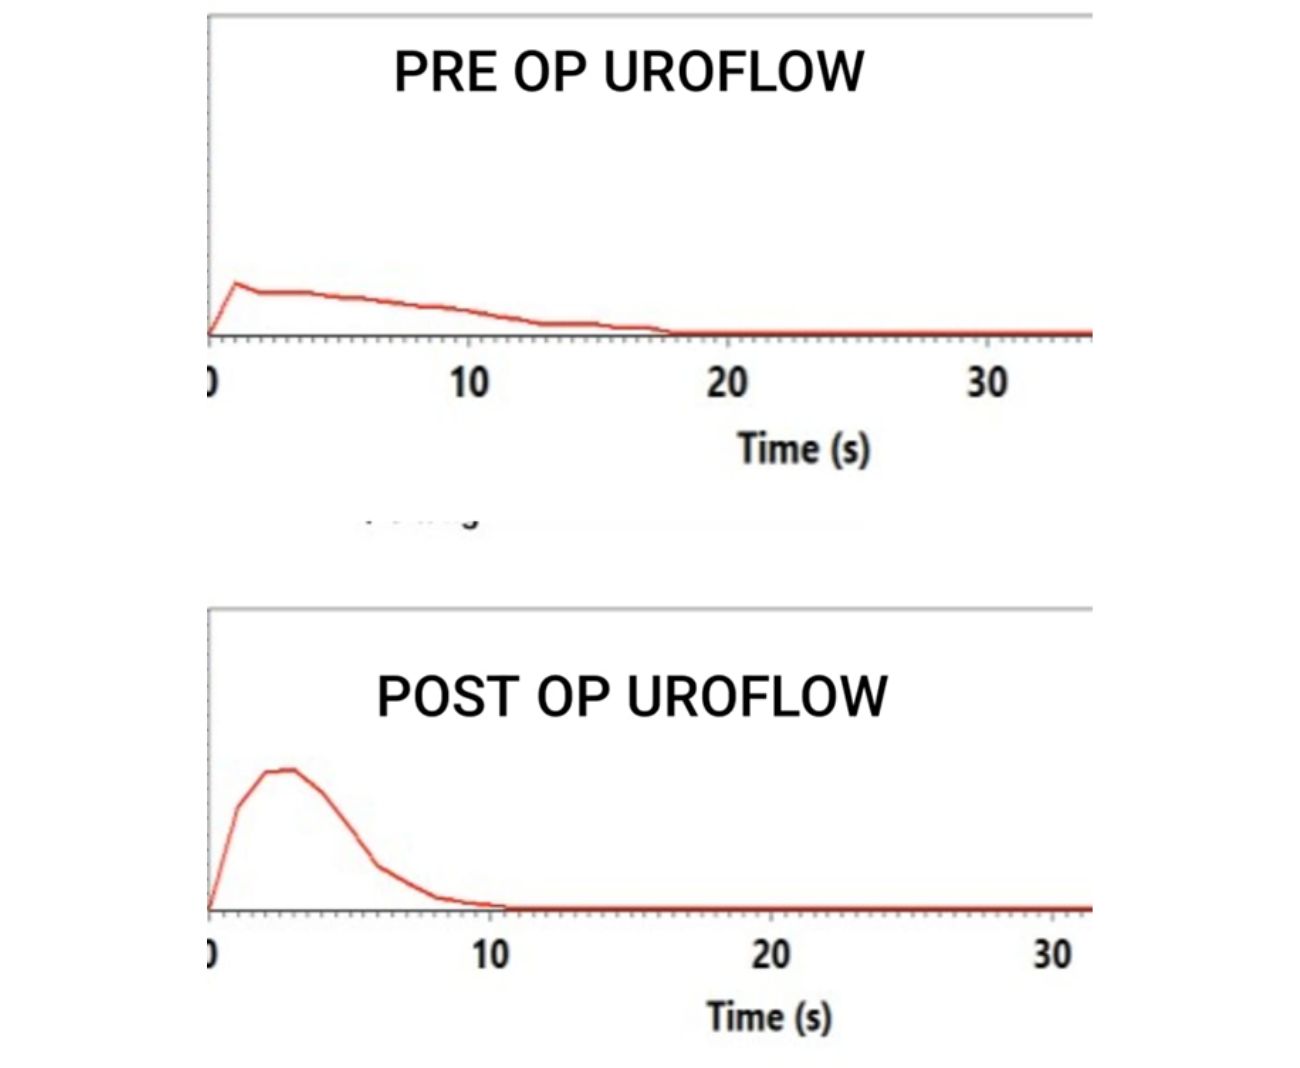

✅ Pyeloplasty (Laparoscopic/Robotic/Open) – The gold-standard surgical treatment that removes the blocked segment and reconstructs the ureter for long-term relief.